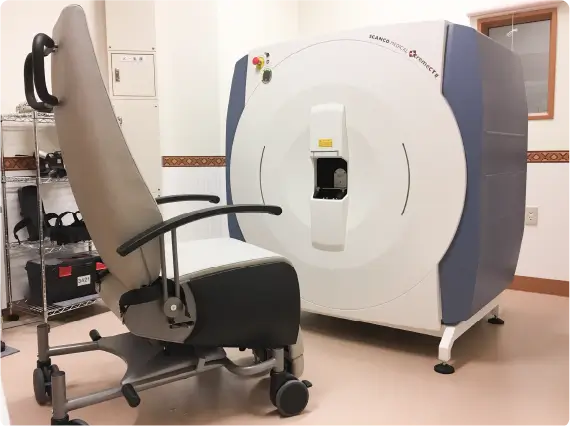

HR-pQCT装置(高解像度の末梢骨用の定量的CT装置)

HR-pQCT(High-Resolution peripheral Quantitative Computed Tomography)は前腕や下腿の骨を高解像度で撮影し、骨の内部構造を三次元的に評価することができる最先端計測機器です。従来の骨密度検査(DEXA)では評価しきれなかった、「骨の質」や骨の細かい構造の変化を捉えることができ、より高度な骨粗鬆症の診断・治療効果の判定に役立ちます。HR-pQCTは研究機関や専門病院など、限られた施設でしか導入されておらず、先進的な骨の評価を受けられることが当院の強みのひとつです。大学や研究機関とも共同研究を行っています。実際に患者さまの骨の状態を詳しく評価し、テーラーメードの骨の治療を行うようにしています。

【撮影画像】

これらの装置を治療過程において効果的に用いることで、より効果的な医療を提供できると考えております。骨粗鬆症について、一緒に計画を立て「コツコツ」と治療をしていきましょう。